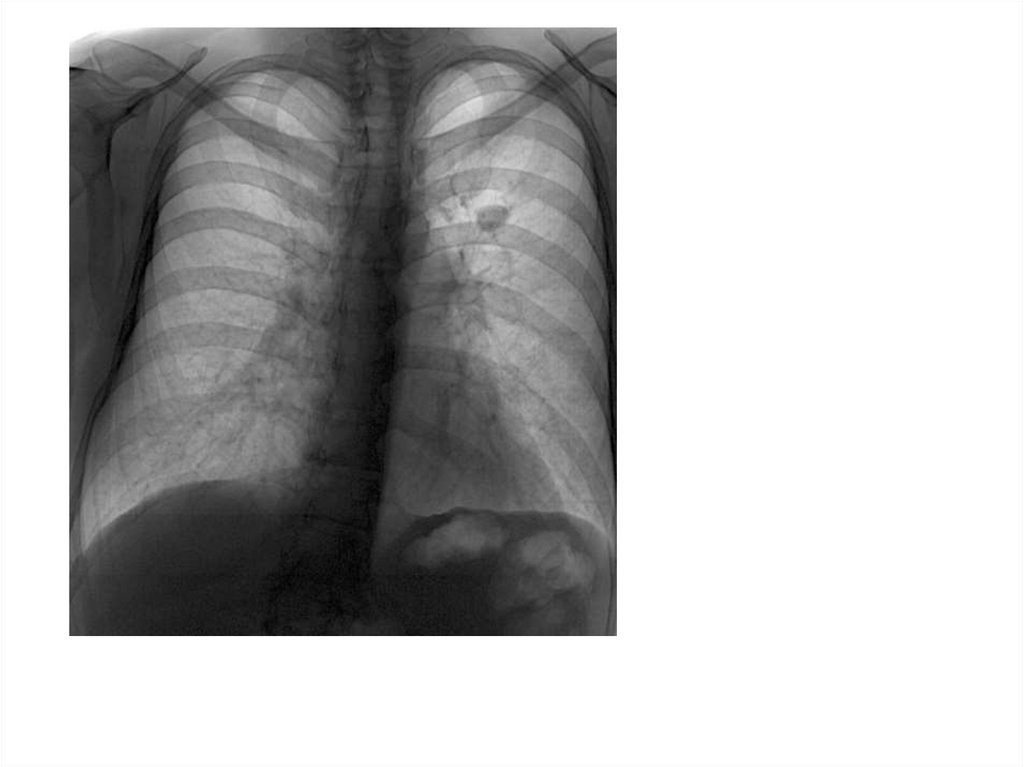

Рентгенограмма № 3

32. Рентгенограмма № 3